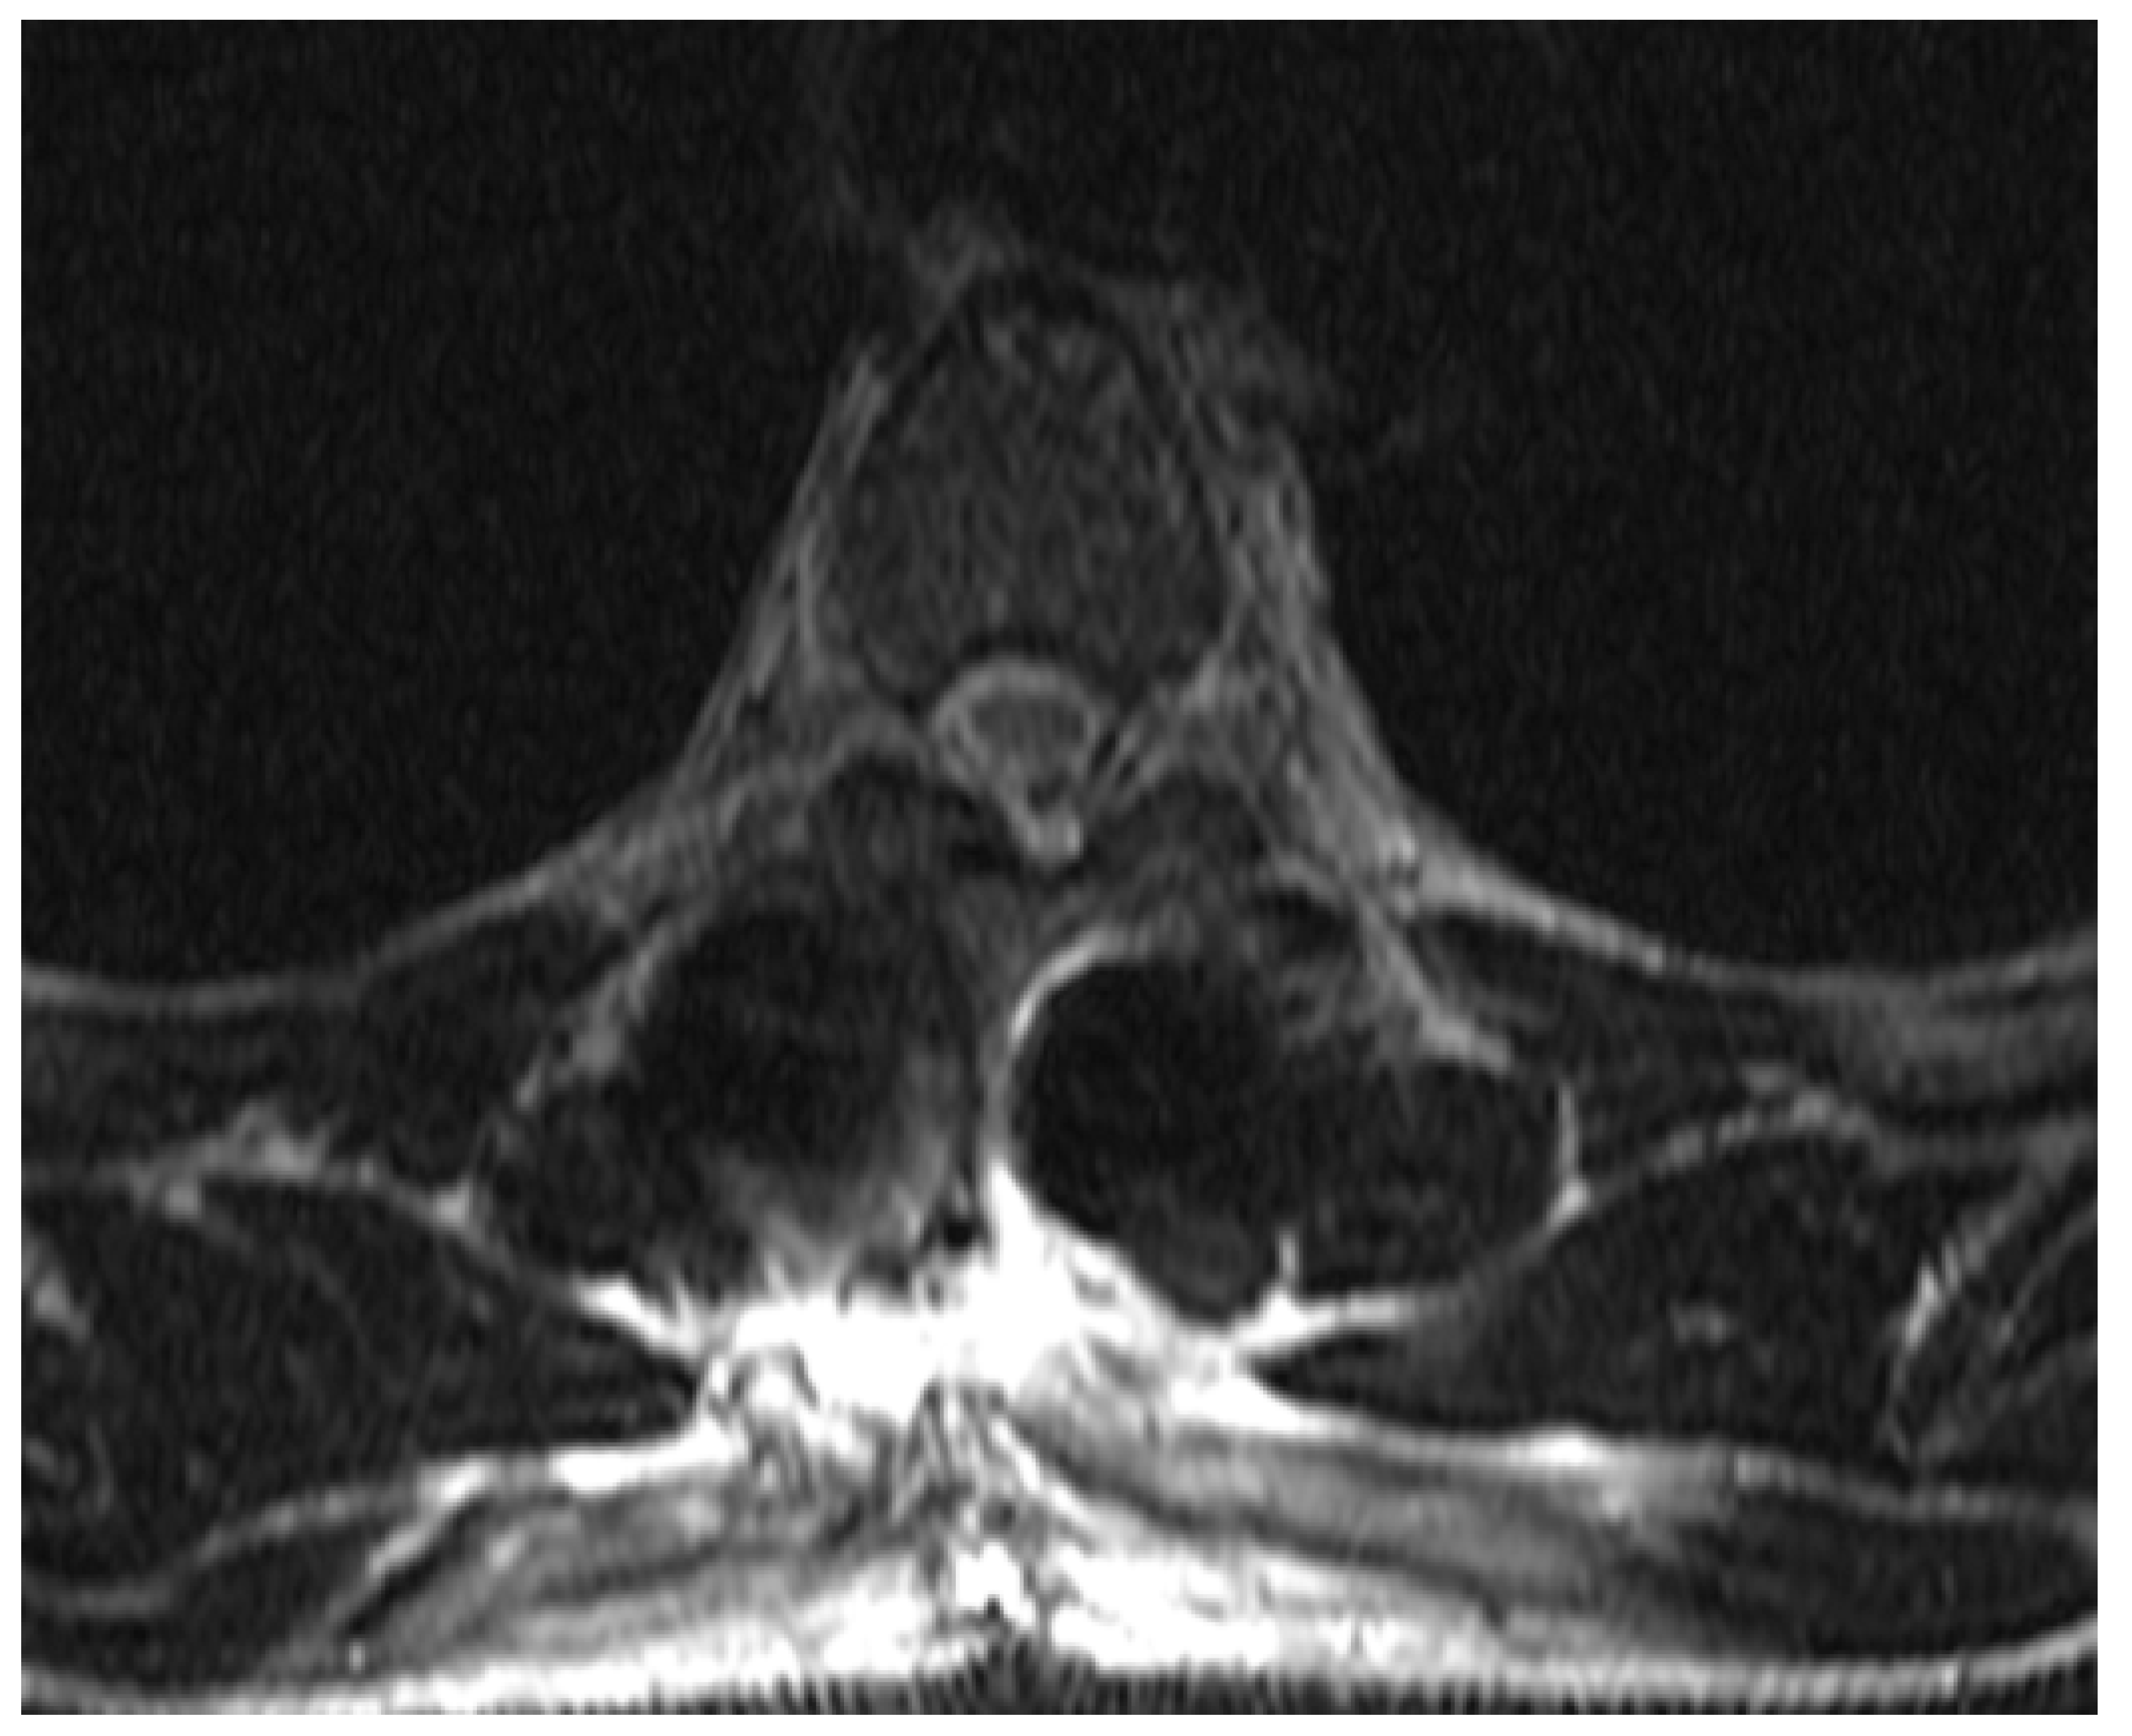

2. Case Report